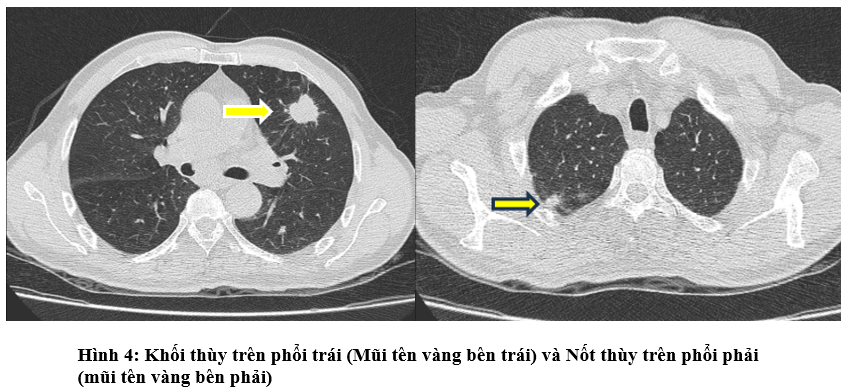

- Chụp Cắt Lớp Vi Tính Ngực: Phổi trái: thùy trên có khối ~ 27x30mm, bờ tua gai.Phổi phải: đỉnh phổi thùy trên có nốt đặc ~ 10mm.Tuyến thượng thận trái có khối ~ 21x32mm.Trung thất vị trí ngã ba khí phế quản và cửa sổ chủ phổi có vài hạch, hạch lớn nhất kích thước 10x13mm

- Chụp PET/CT: Hình ảnh dày thành đại tràng góc lách, dày nhất 18mm, trên đoạn 41mm, tăng chuyển hóa, thâm nhiễm mỡ xung quanh. Vài hạch ở cạnh tổn thương đại tràng, cạnh động mạch chủ bụng và cạnh thân tụy tăng chuyển hóa, khả năng do di căn. Hình ảnh tổn thương bờ tua gai ở S3 phổi trái, kích thước 31x26x22mm, tăng chuyển hóa, khả năng là tổn thương ác tính nguyên phát. Hình ảnh vài hạch trung thất nhóm 5, 6, 7, hạch thượng đòn Phải tăng chuyển hóa, khả năng do di căn. Hình ảnh vài nốt bán đặc và kính mờ rải rác nhu mô phổi 2 bên, có nốt tăng chuyển hóa, khả năng do di căn

- Ung thư đại tràng ngang cT4N1M1 (di căn hạch ổ bụng) - Ung thư thùy trên phổi trái cT4N3M1 (di căn phổi phải, tuyến thượng thận trái)

+ Tại hạch cổ phải: Ung thư biểu mô di căn nguồn gốc tại phổi. EGFR(-)